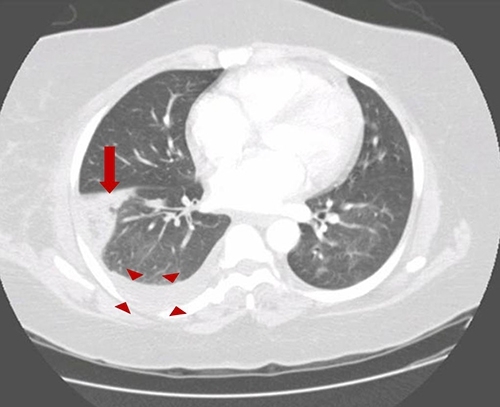

Pulmonary emboli: Approximately 10% of patients with PE have occlusion of a peripheral pulmonary artery by thrombus, causing pulmonary infarction. These small peripheral thrombi are more likely to cause pleuritic chest pain and hemoptysis, due to inflammation and irritation of the lung parenchyma and adjacent visceral and parietal pleura. CT shows wedge shaped lungs and pleural effusion:

contrast CT: pulmonary artery filling defect: